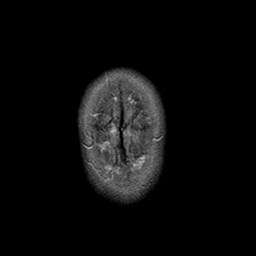

Stroke:T2-weighted MR #1 -- Slice #23

[Home][Help][Clinical] Slice 23